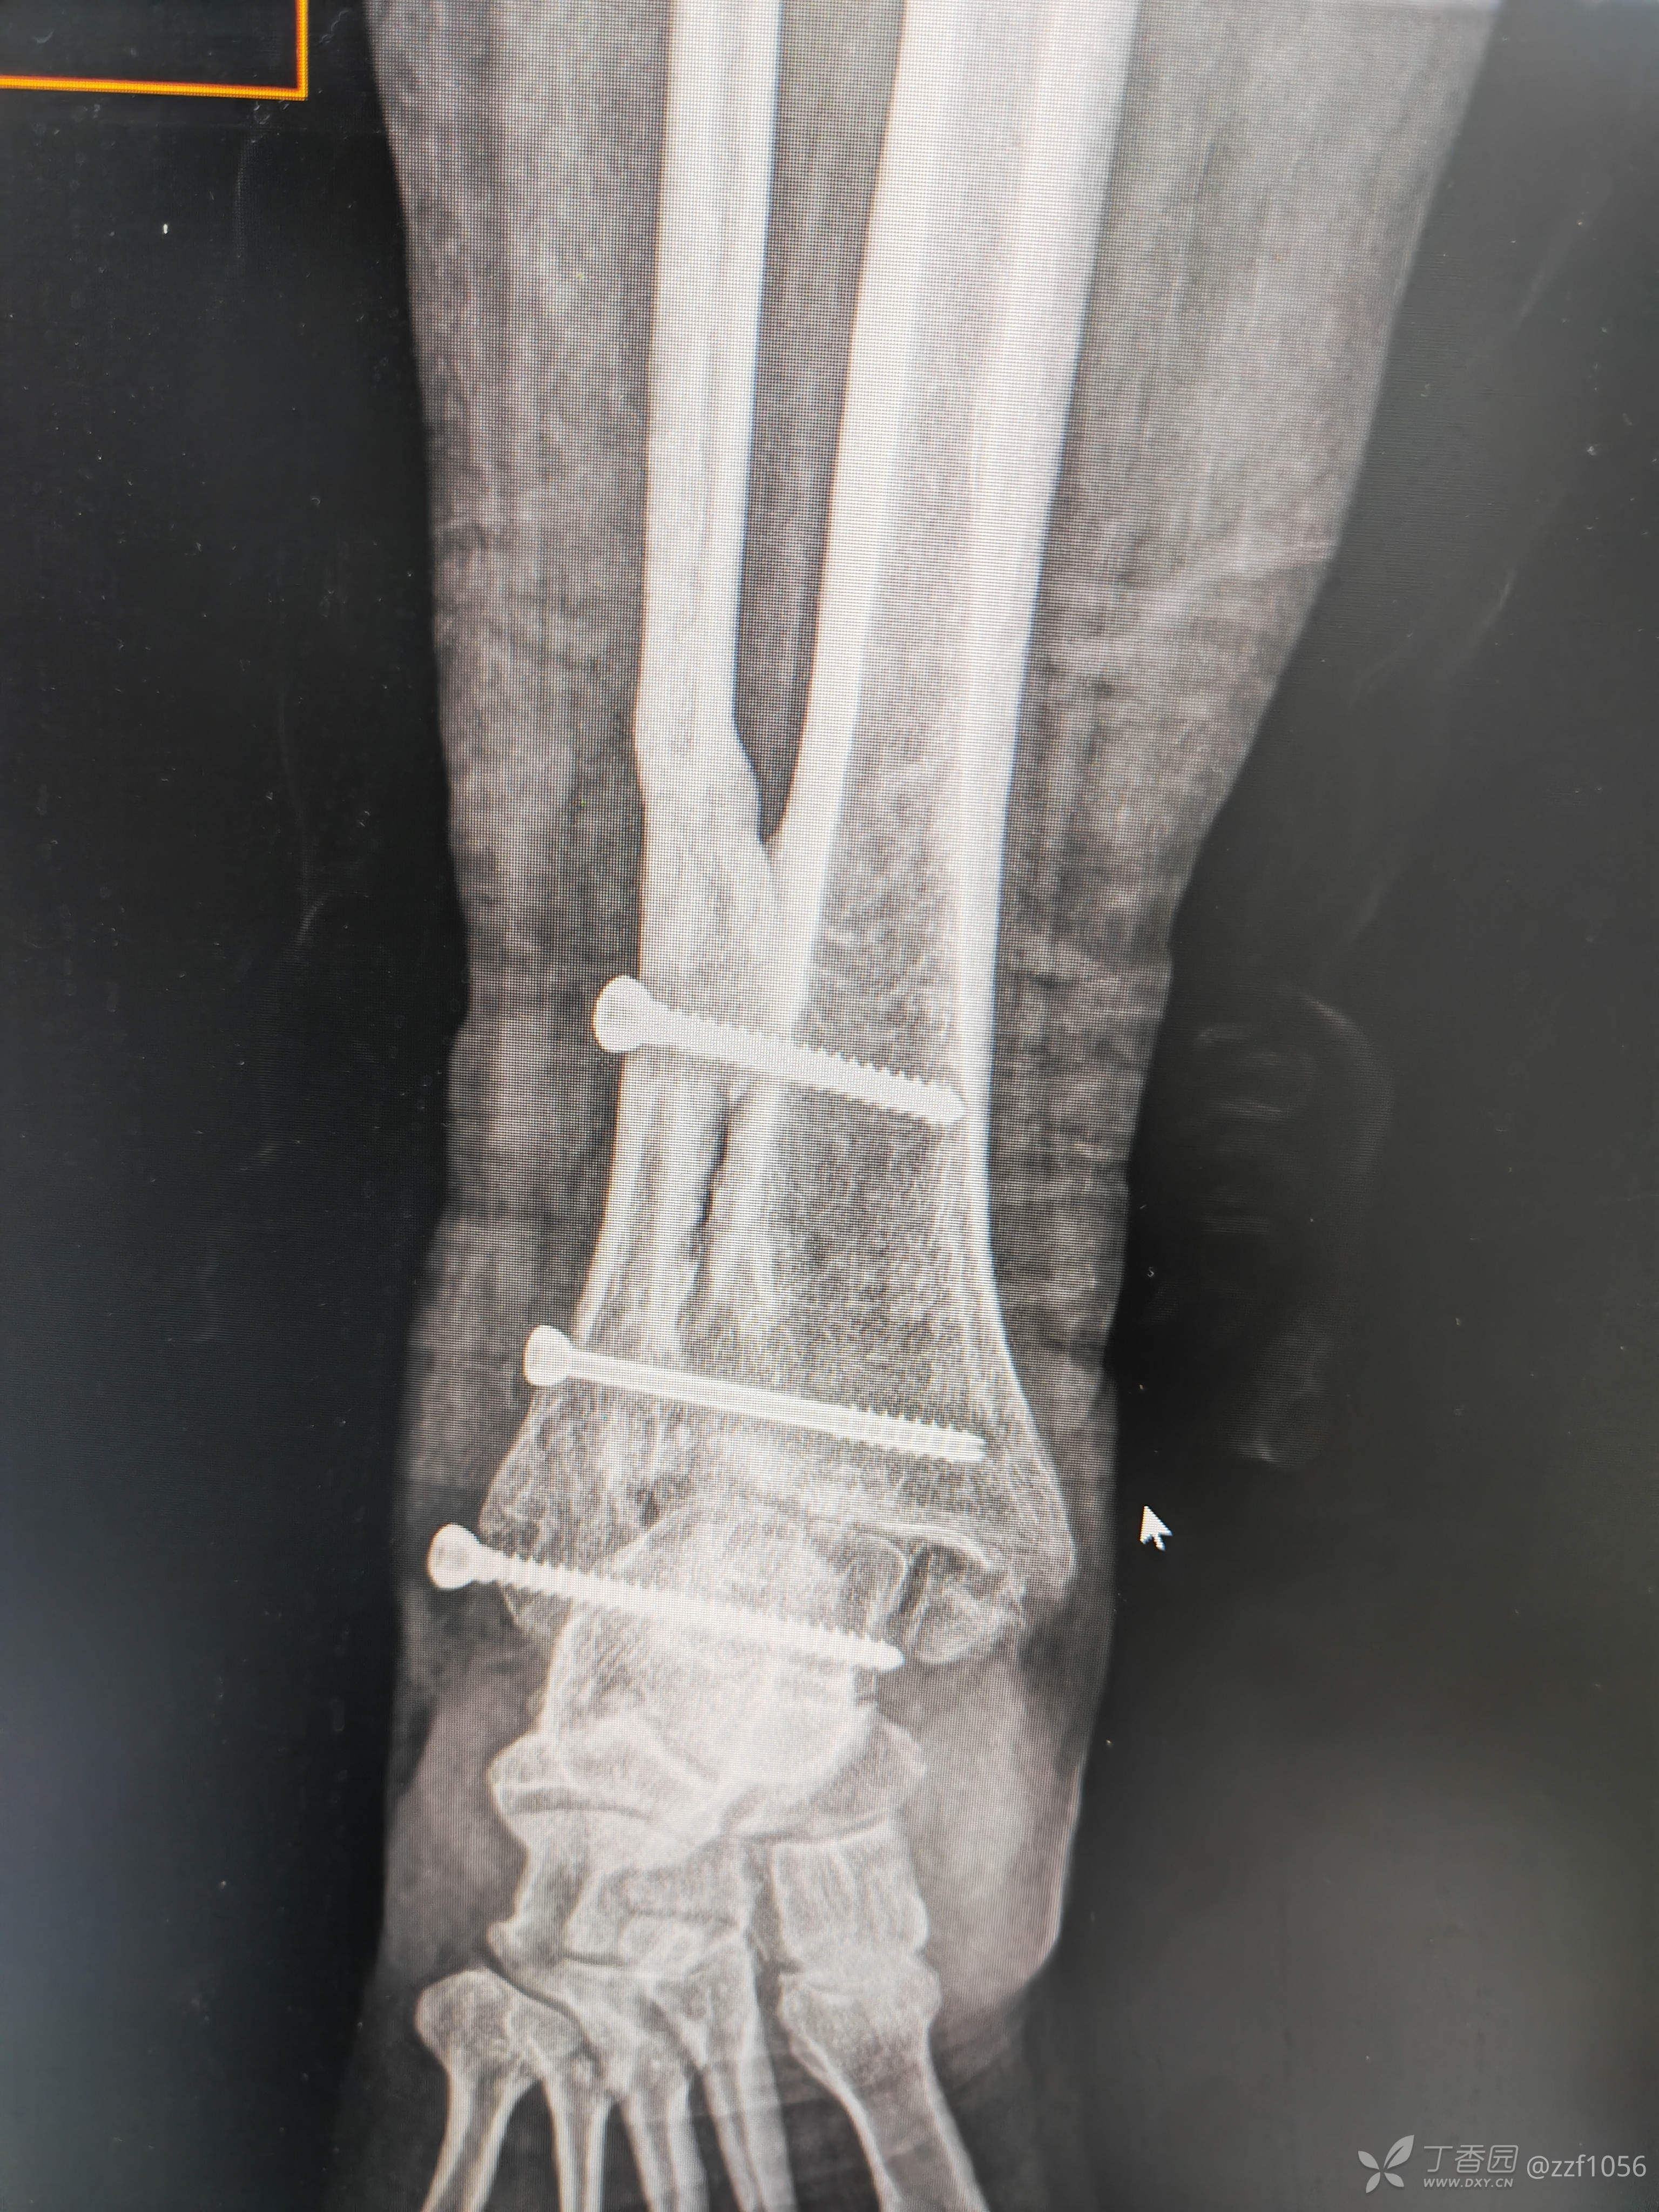

入院诊断:右踝关节骨折术后畸形融合,内固定存留

入院完善检查,拟定行右踝内固定取出、融合翻修术。

三钉定乾坤吗?

术后

就备了一块融合钢板,偏长了点